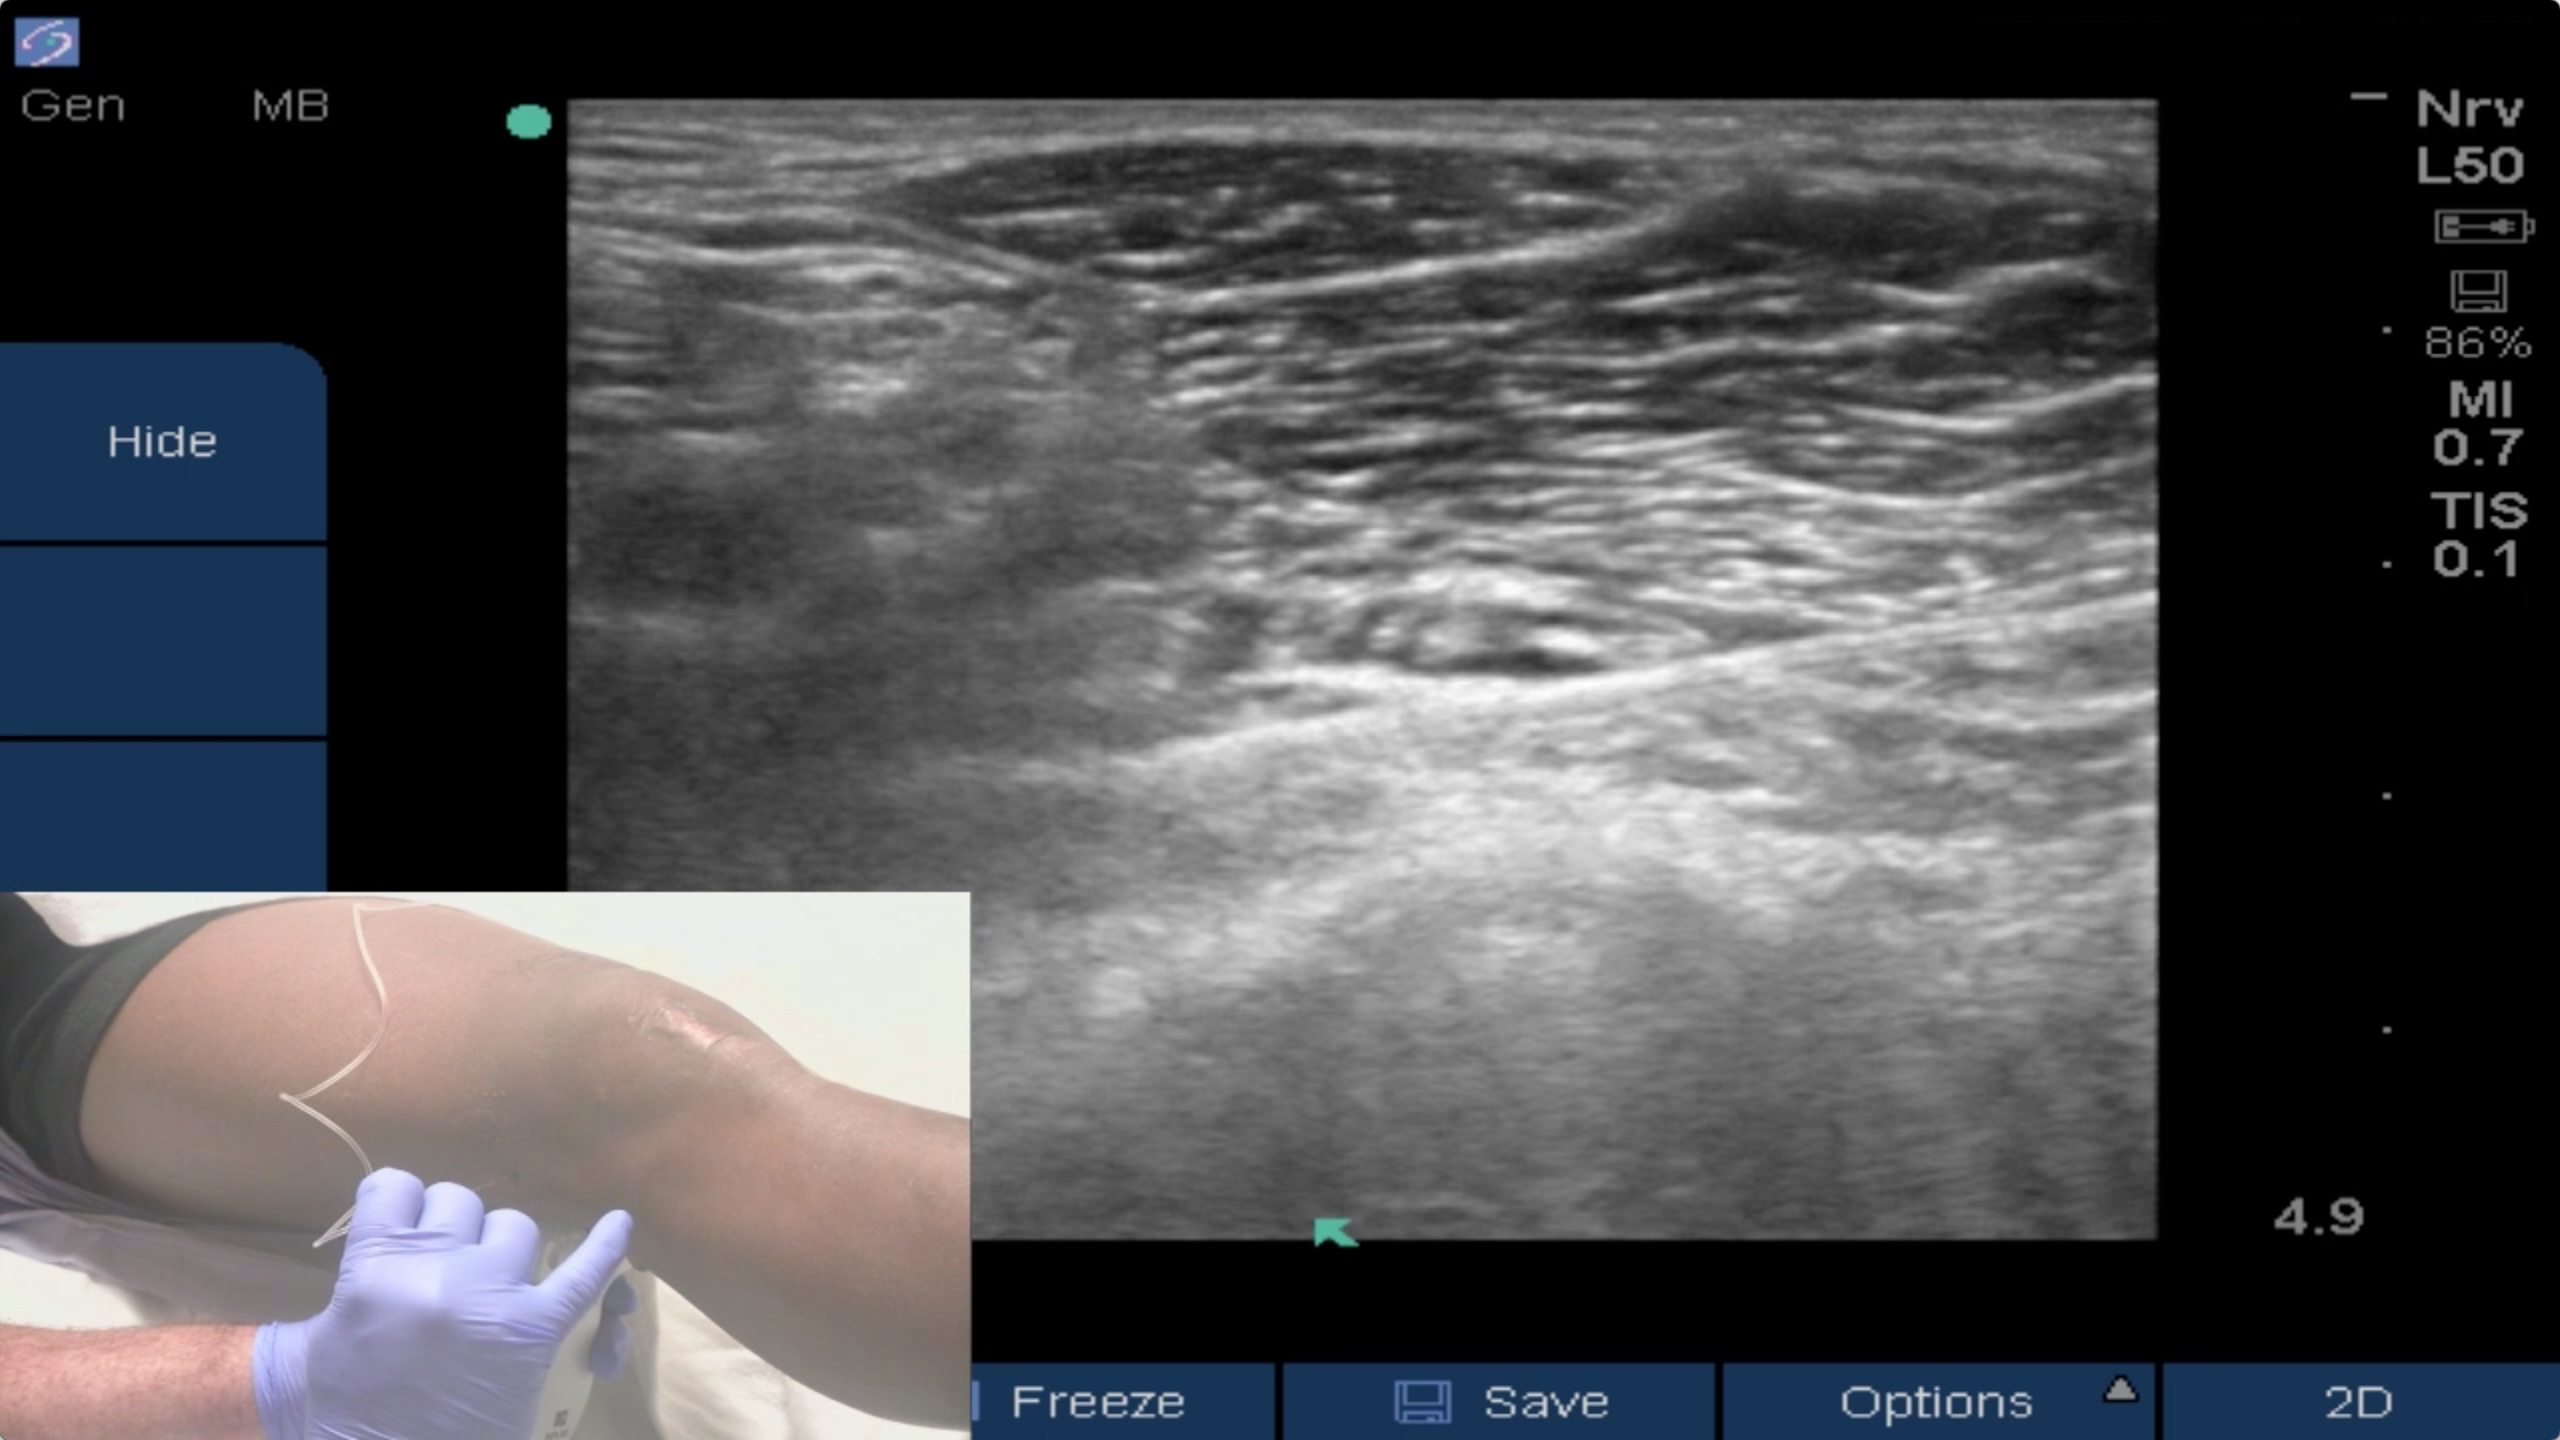

Ultrasound guided iPACK (Interspace between the Popliteal Artery & Capsule of the Knee) block procedure videos.

In this new BLOCKJOCKS BLOCK OF THE DAY video Dr. Greg Hickman performs an ultrasound-guided iPACK block, injecting local anesthetic in the Interspace between the Popliteal Artery and the Capsule of the Knee to achieve posterior analgesia for ACL reconstruction. This approach has gained popularit...